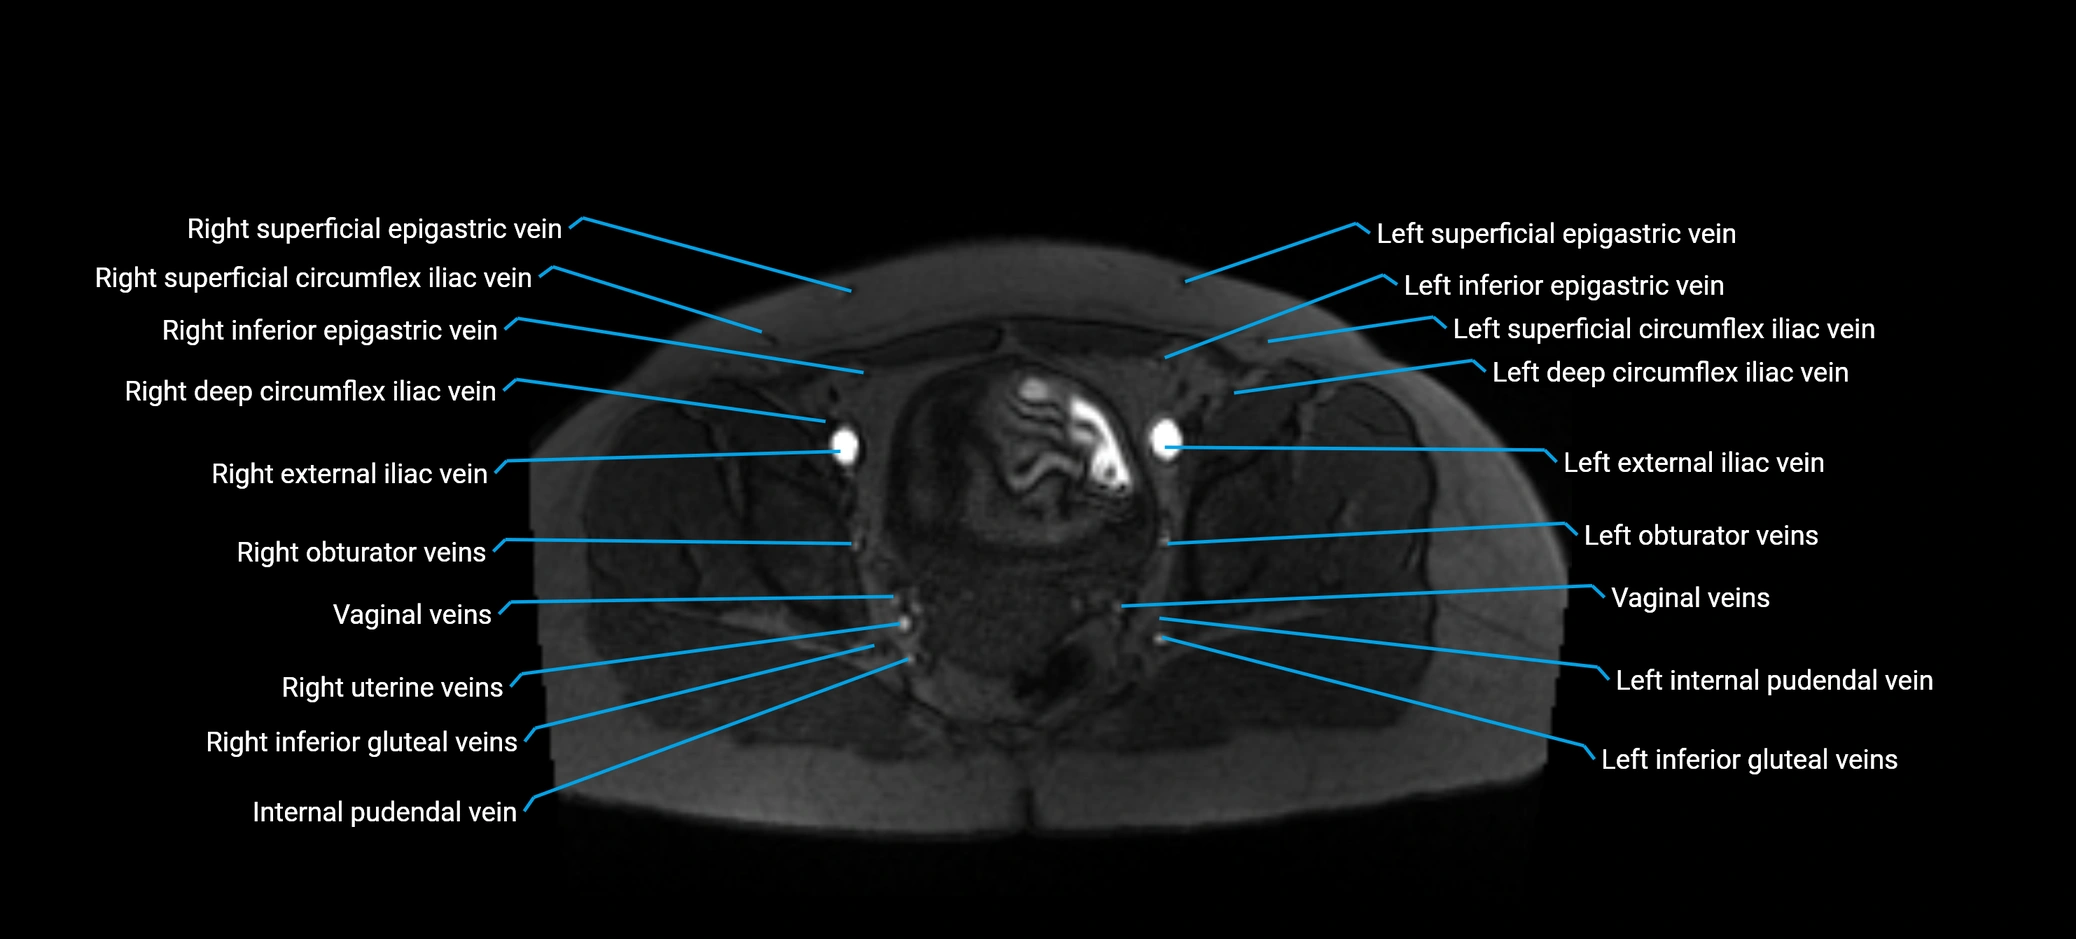

MRI image

image